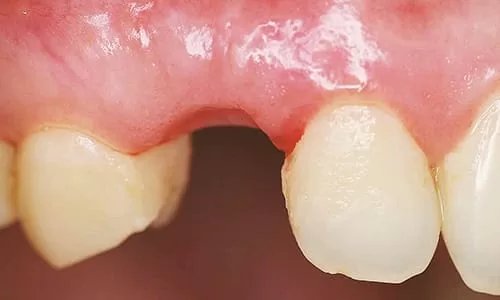

植牙前拔除乳牙後

- 拔除右上犬齒處之乳齒。